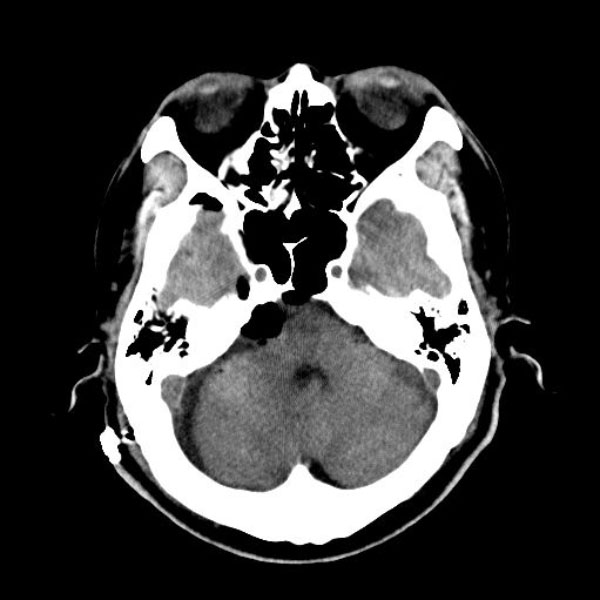

手術後

(CT)